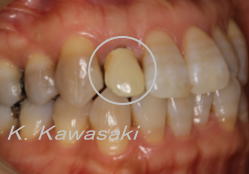

| 前歯の作り直しを希望して来院されました。色・形態・大きさなど審美的ではありません。 |

精密検査の結果、骨の中で歯が割れていることが判明しました。残念ながら抜歯となりました。 |

通常抜歯した部分の歯茎はすぐに痩せてしまいます(○の部分)。外科的に歯茎を増やさなければ美しい歯を入れることはできません。 |

| 外科処置後、ジルコニアのクラウンを装着し審美性を回復しました。 |

どの歯を抜歯したかおわかりでしょうか? |

黄色の○の部分が抜歯した歯です。 |